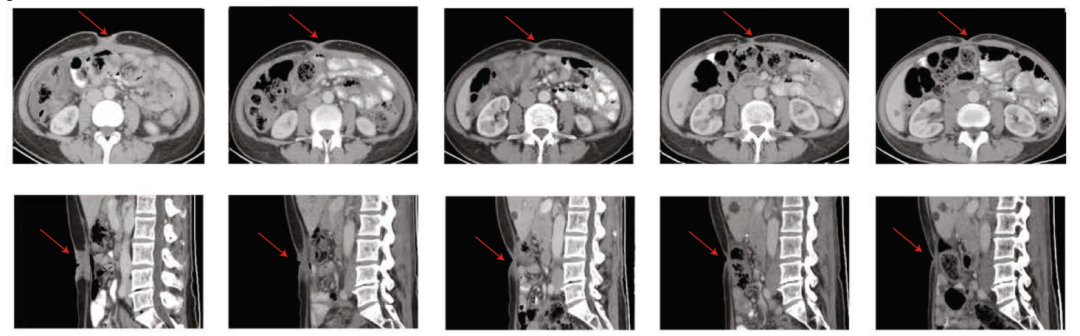

本次1期临床试验的中期研究结果显示:在接受治疗的37名癌症患者中,有30例患者出现肿瘤消退!所有患者的疾病控制率(DCR)达到73%;患者的总体缓解率(ORR)达到了48.6%;并且,患者的6个月总生存率高达80.1%!治疗效果相当显著。

对于接受治疗的胃癌患者来说,总体缓解率和疾病控制率分别达到了75%和57.1%,6个月的总生存率达到了81.2%,略高于总体的治疗数据。其中在对CT041治疗有反应的16名胃癌患者中,有14名患者在接受第一次CAR-T细胞治疗后的第四周就达到了部分缓解。